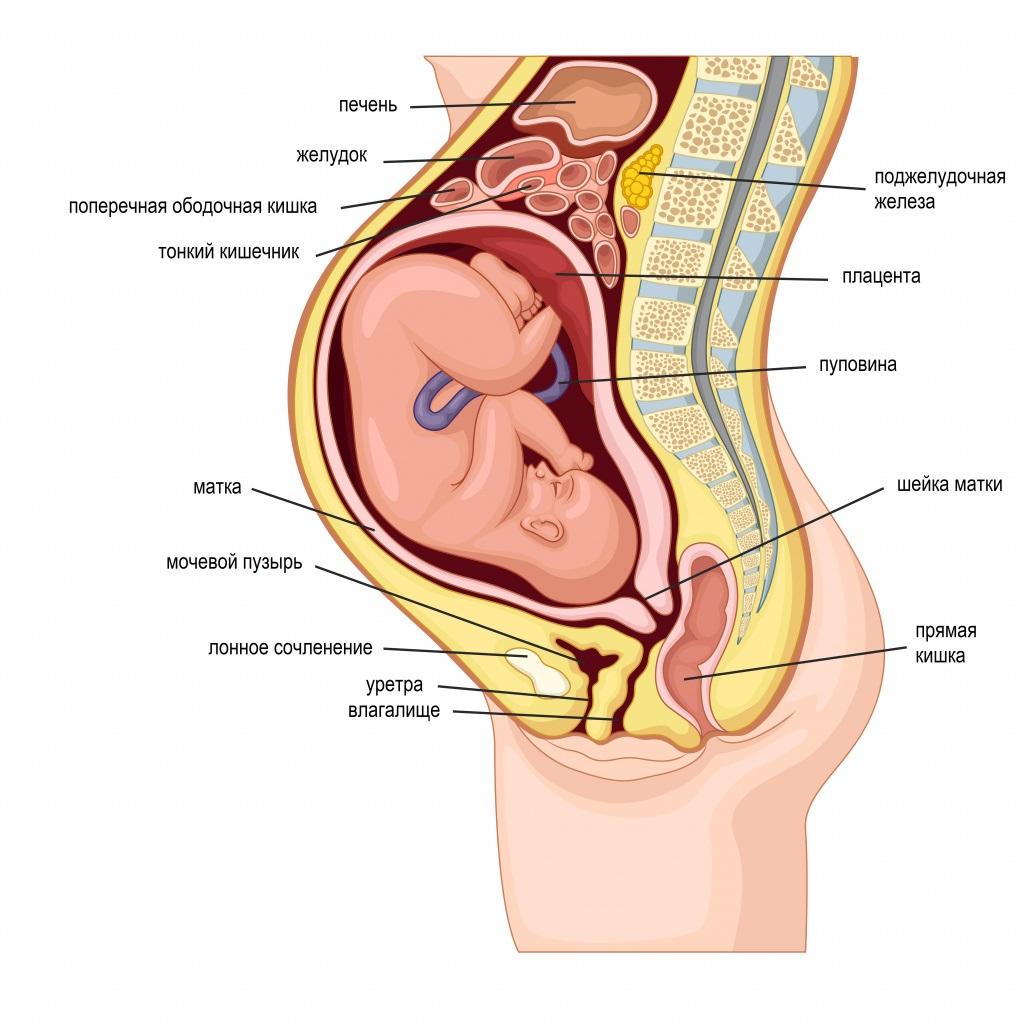

Физиология беременности: строение органов

Раздел: Моменты озарения